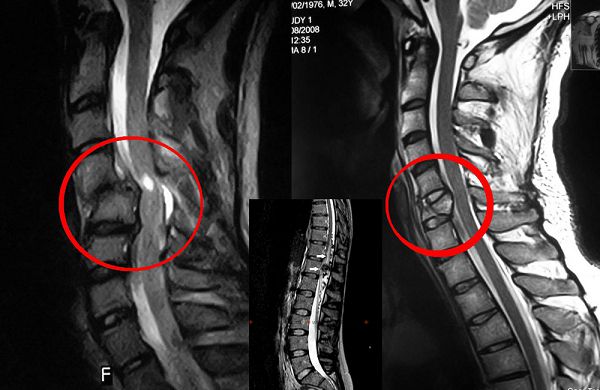

- Магнитно-резонансная томография (МРТ) помогает установить локализацию и степень деформации сосудов.